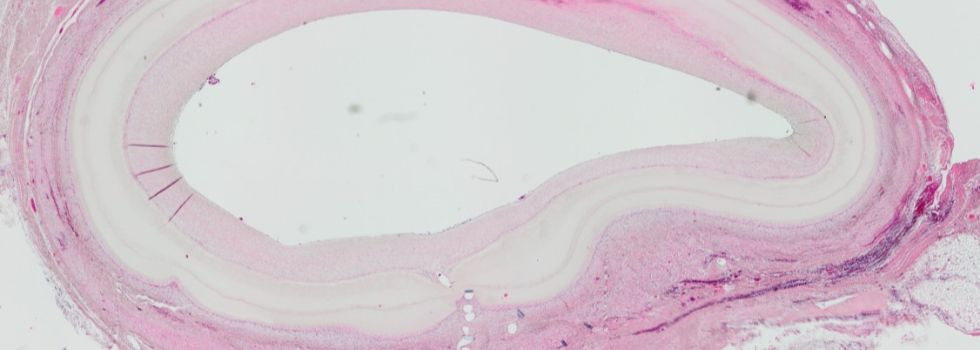

1. Cardiovascular tissue engineering

Cardiovascular Tissue Engineering

Artificial Bypass - Tissue Engineering in Cardiac Surgery

With a share of more than 50%, bypass surgery represents the largest share in the cardiac surgery portfolio. Every year alone in the US and Germany together… more.